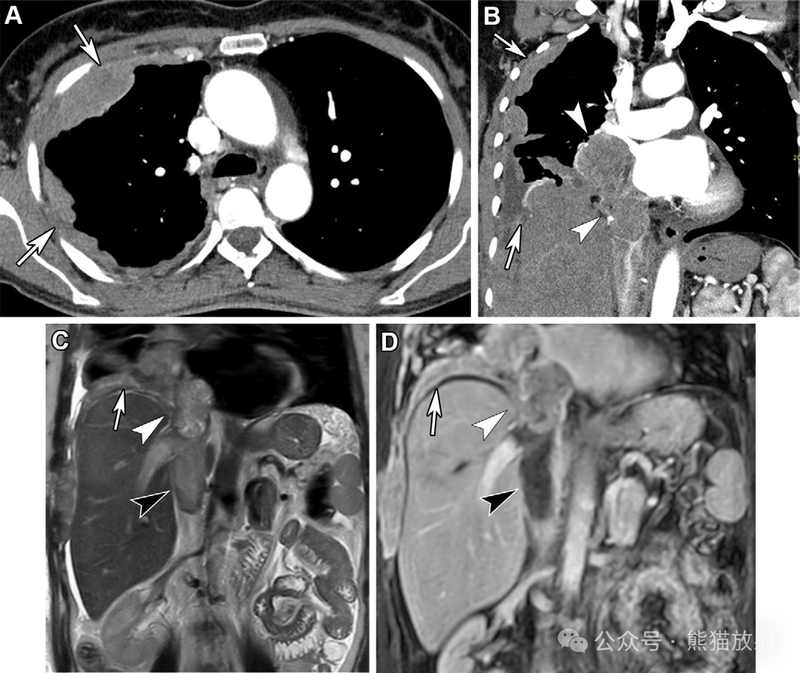

62岁女性,胸膜间皮瘤。(A,B) 轴位 (A) 和冠状 (B) 对比增强胸部 CT 图像显示右侧胸膜肿块(箭),不均质强化,并侵及纵隔和心脏,下腔静脉 (IVC) 血栓形成(B箭头)。(C,D) 下胸部和上腹部的冠状T2WI(C) 和对比增强 (D) MR 图像显示胸膜肿块(箭头)侵及心脏和心内膜,伴瘤栓(白箭头)和血栓 (黑箭头)。MRI有助于评估纵隔和血管的受累情况。